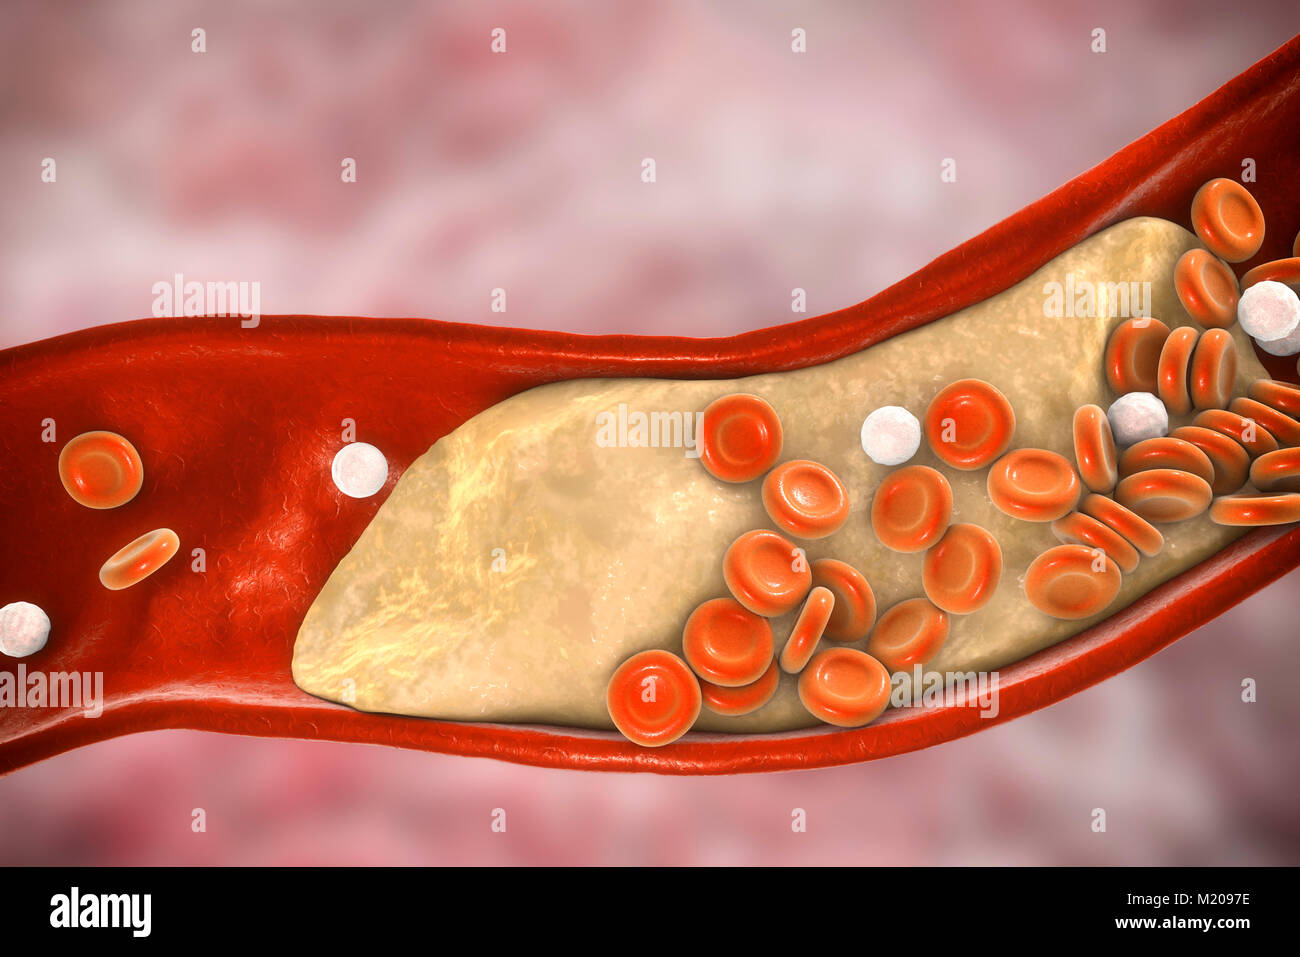

Atheromatous plaque inside blood vessel, computer illustration. A cholesterol atheroma is causing a narrowing of an artery (atherosclerosis). Stock Photohttps://www.alamy.com/image-license-details/?v=1https://www.alamy.com/stock-photo-atheromatous-plaque-inside-blood-vessel-computer-illustration-a-cholesterol-173340259.html

Atheromatous plaque inside blood vessel, computer illustration. A cholesterol atheroma is causing a narrowing of an artery (atherosclerosis). Stock Photohttps://www.alamy.com/image-license-details/?v=1https://www.alamy.com/stock-photo-atheromatous-plaque-inside-blood-vessel-computer-illustration-a-cholesterol-173340259.htmlRFM2097F–Atheromatous plaque inside blood vessel, computer illustration. A cholesterol atheroma is causing a narrowing of an artery (atherosclerosis).

Atheromatous plaque inside blood vessel, computer illustration. A cholesterol atheroma is causing a narrowing of an artery (atherosclerosis). Stock Photohttps://www.alamy.com/image-license-details/?v=1https://www.alamy.com/stock-photo-atheromatous-plaque-inside-blood-vessel-computer-illustration-a-cholesterol-173340258.html

Atheromatous plaque inside blood vessel, computer illustration. A cholesterol atheroma is causing a narrowing of an artery (atherosclerosis). Stock Photohttps://www.alamy.com/image-license-details/?v=1https://www.alamy.com/stock-photo-atheromatous-plaque-inside-blood-vessel-computer-illustration-a-cholesterol-173340258.htmlRFM2097E–Atheromatous plaque inside blood vessel, computer illustration. A cholesterol atheroma is causing a narrowing of an artery (atherosclerosis).

Atheromatous plaque inside blood vessel, computer illustration. A cholesterol atheroma is causing a narrowing of an artery (atherosclerosis). Stock Photohttps://www.alamy.com/image-license-details/?v=1https://www.alamy.com/stock-photo-atheromatous-plaque-inside-blood-vessel-computer-illustration-a-cholesterol-173340260.html

Atheromatous plaque inside blood vessel, computer illustration. A cholesterol atheroma is causing a narrowing of an artery (atherosclerosis). Stock Photohttps://www.alamy.com/image-license-details/?v=1https://www.alamy.com/stock-photo-atheromatous-plaque-inside-blood-vessel-computer-illustration-a-cholesterol-173340260.htmlRFM2097G–Atheromatous plaque inside blood vessel, computer illustration. A cholesterol atheroma is causing a narrowing of an artery (atherosclerosis).

Atheromatous plaque inside blood vessel, computer illustration. A cholesterol atheroma is causing a narrowing of an artery (atherosclerosis). Stock Photohttps://www.alamy.com/image-license-details/?v=1https://www.alamy.com/stock-photo-atheromatous-plaque-inside-blood-vessel-computer-illustration-a-cholesterol-173340255.html

Atheromatous plaque inside blood vessel, computer illustration. A cholesterol atheroma is causing a narrowing of an artery (atherosclerosis). Stock Photohttps://www.alamy.com/image-license-details/?v=1https://www.alamy.com/stock-photo-atheromatous-plaque-inside-blood-vessel-computer-illustration-a-cholesterol-173340255.htmlRFM2097B–Atheromatous plaque inside blood vessel, computer illustration. A cholesterol atheroma is causing a narrowing of an artery (atherosclerosis).

Atheromatous plaque inside blood vessel, computer illustration. A cholesterol atheroma is causing a narrowing of an artery (atherosclerosis). Stock Photohttps://www.alamy.com/image-license-details/?v=1https://www.alamy.com/stock-photo-atheromatous-plaque-inside-blood-vessel-computer-illustration-a-cholesterol-173340254.html

Atheromatous plaque inside blood vessel, computer illustration. A cholesterol atheroma is causing a narrowing of an artery (atherosclerosis). Stock Photohttps://www.alamy.com/image-license-details/?v=1https://www.alamy.com/stock-photo-atheromatous-plaque-inside-blood-vessel-computer-illustration-a-cholesterol-173340254.htmlRFM2097A–Atheromatous plaque inside blood vessel, computer illustration. A cholesterol atheroma is causing a narrowing of an artery (atherosclerosis).